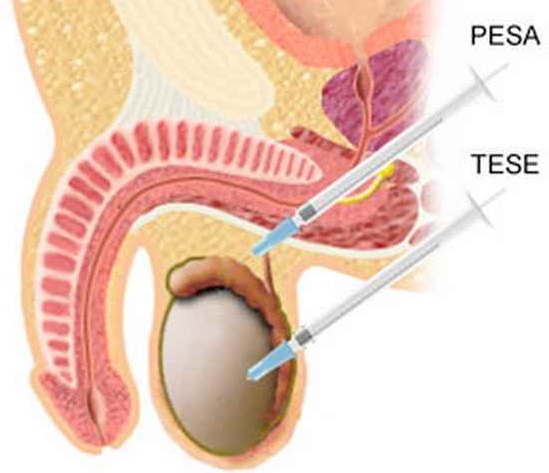

ПовечеПункция на тестисите

Публикувано на: 09.01.2007 b>Показания, резултати Размерът на пениса често е предмет на дискусия между мъжете, но за размера...

Повече